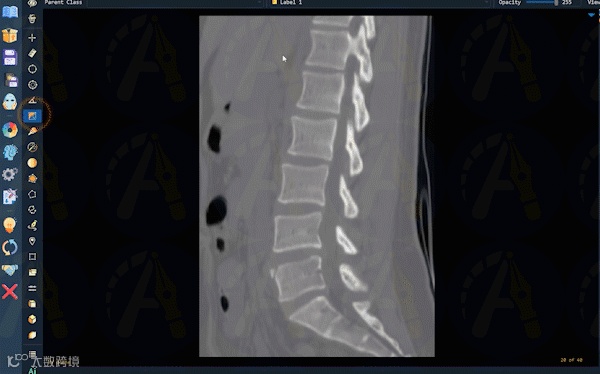

AutoSeg已在CT,MRI,超声,X-ray,PET,扫描电镜,病理,涂片,内窥镜等影像模态的多种解剖结构和病灶上验证和使用。AutoSeg的标注结果可便捷编辑修改,以方便用户微调和快速确认。如下是AutoSeg在多样化的影像和解剖结构上的应用展示: